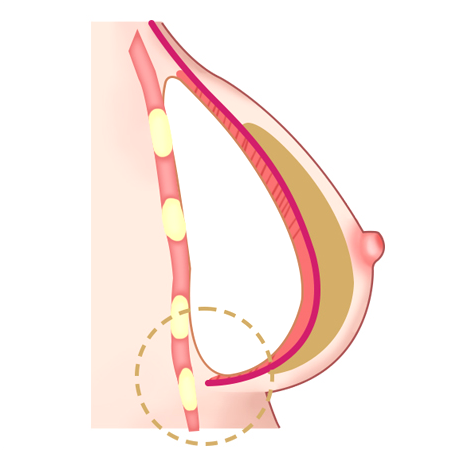

ผ่าตัดส่วนล่างของกล้ามเนื้อหน้าอกส่วนบน

เมื่อกรีดกล้ามเนื้อออก เนื่องจากแรงดึงของกล้ามเนื้อ ทำให้ส่วนบนของกล้ามเนื้อหดตัวและด้านล่างของกล้ามเนื้อจะยึดติดกับด้านล่าง

ใส่ซิลิโคนระหว่างกล้ามเนื้อที่ถูกกรีด ส่วนบนของซิลิโคนอยู่ด้านล่างของกล้ามเนื้อหน้าอก ส่วนล่างของซิลิโคนอยู่ด้านบนของกล้ามเนื้อหน้าอก

วิธีการใส่ท่อนบนของซิลิโคนลงไปใต้กล้ามเนื้อ และท่อนล่างลงไปใต้เยื่อกล้ามเนื้อ

เทคนิคแบบ Dual Plane กล้ามเนื้อหดตัวลงและเคลื่อนที่ขึ้น

ผิวหนังและเนื้อเยื่อที่เชื่อมต่อกันค่อนข้างยืดได้ดี จึงสามารถสร้างเส้นโค้งตามธรรมชาติได้